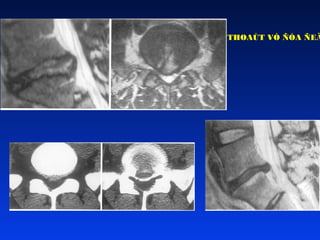

THOAÙT VÒ ÑÓA ÑEÄM Hieám gaëp ôû thieáu nieân, thöôøng thaáy nhaát sau moät gaéng söùc quaù möùc (theå gia ñình)  Thoaùt vò döôùi vaønh suïn thaân soáng ñaëc hieäu ôû thieáu nieân  Ñieàu trò baûo toàn hay phaãu thuaät

THOAÙT VÒ ÑÓA ÑEÄM Sau chaán thöông  Coù theå do di truyeàn

Beânh lyù chung Gaõyvaønh suïn thaân soáng Thoaùt vò ñóa ñeäm Loài ñóa ñeäm